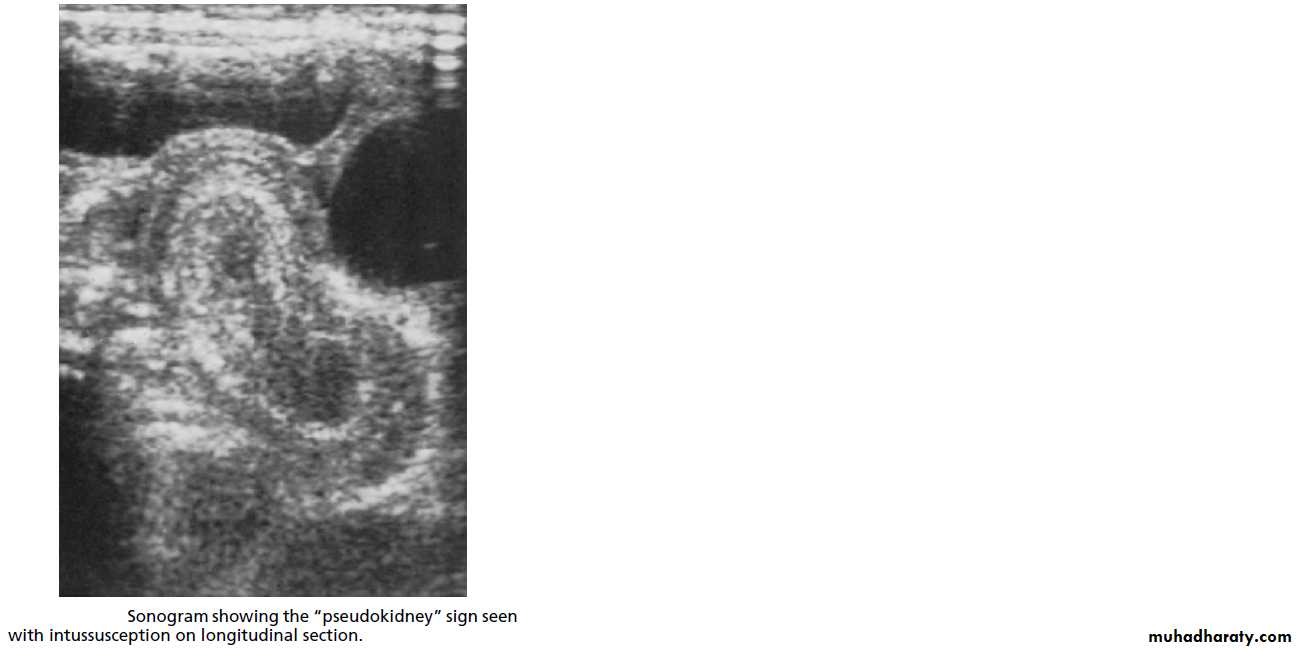

2. US